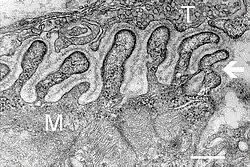

![]() Electron micrograph showing a cross section through the neuromuscular junction. T is the axon terminal, M is the muscle fiber. The arrow shows junctional folds with basal lamina. Active zones are visible on the tips between the folds. Scale is 0.3 μm. Source: NIMH | |